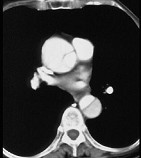

男,64岁,突感胸部剧痛2h,呈撕裂样,并向背部放射,有高血压病史10年,含服硝酸甘油3片不能缓解,CT检查如图所示。首先应考虑的诊断是 ( ) XN-09481.jpg XN-09482.jpg XN-09483.jpg

• A.主动脉夹层